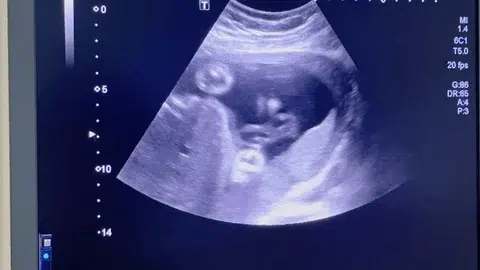

2D Ultrasound

2D Ultrasound Explained: Procedure, Uses & Benefits

A 2D ultrasound is one of the most common and safest medical imaging methods used today. It helps doctors see inside your body using sound waves, not radiation. This quick, painless test is often done during pregnancy or for examining internal organs. In just a few minutes, it gives doctors valuable information to help diagnose, monitor, or confirm medical conditions confidently.

2D ultrasound, also called a sonography or ultrasound scan, is a diagnostic imaging technique that creates two-dimensional images of the body. It works by sending sound waves through soft tissues and capturing the echoes that bounce back. These echoes are converted into real-time images on a monitor, allowing doctors to see organs, tissues, and blood flow.

• Pregnancy ultrasound: To confirm pregnancy, estimate gestational age, monitor fetal growth, and check the baby’s position or heartbeat.

• Pregnancy scans: Show fetal position, heartbeat, and growth progress.